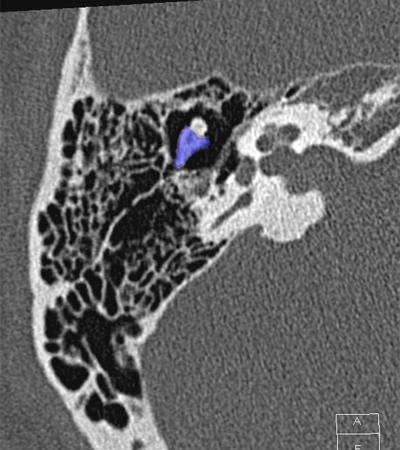

Cochlea Internal auditory canal Vestibule Posterior semicircular canal Head of malleus Body of incus Incudomallear joint